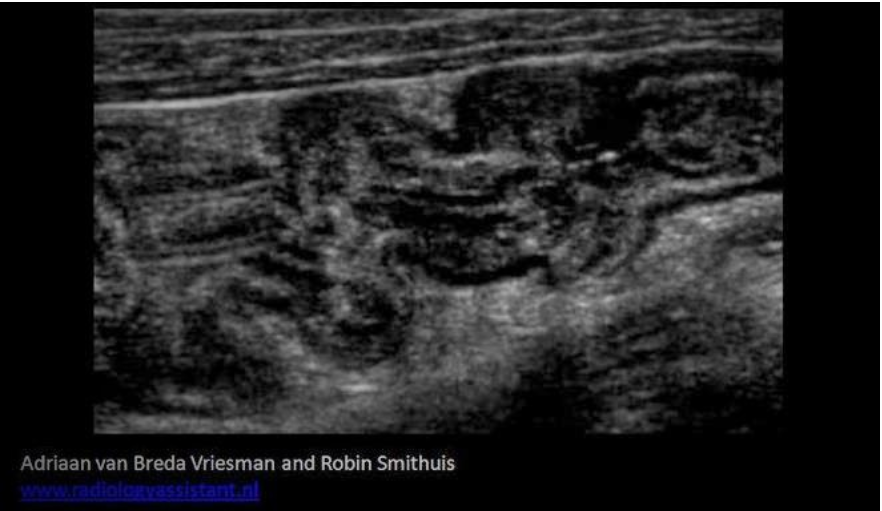

A 50yr old male presents with RLQ pain, watery diarrhea and a low grade fever. The ultrasound exam demonstrates a prominent lymph node in the area of pain and the image below was also obtained at the area of pain. These findings are most consistent with?

A. Colitis

The patient symptoms are related to an infection, most likely in the RLQ area of pain. Colitis will cause the thickening of the bowel wall seen on the image. The haustra are visible which indicates a colon segment and not the appendix. Irritable bowel syndrome (IBS) is a diffuse functional disorder of the colon that would not cause a fever or enlarged nodes.